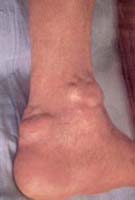

Hombre de 35 años quien consultó por una historia de desarrollo gradual de múltiples nódulos subcutáneos indoloros en varias articulaciones, rodillas, codos, muñecas, y tobillos. No existía antecedente de previo compromiso articular.

Al examen físico presentaba múltiples nódulos subcutáneos entre 0,5 y 3 cm, móviles (Figura 1), indoloros predominantemente sobre las superficies extensoras. No se evidenció edema articular, rigidez ni otros signos inflamatorios. Los exámenes de laboratorio incluyendo cuadro hemático, pruebas de función renal y química sanguínea se encontraron en límites normales. Los niveles de ácido úrico se encontraron en 6,5 mg/dl.

Figura 1. Se aprecian nódulos múltiples en area perimaleolar.